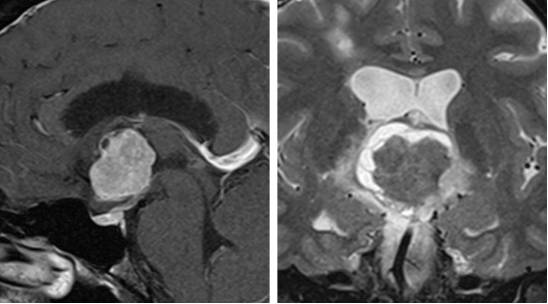

图13. 如图所示为典型的脊索样胶质瘤。